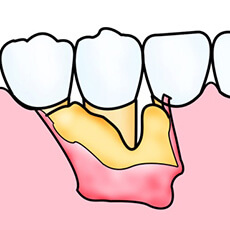

歯周病の進行により、歯を支えている骨は溶けてしまいます。通常、一度失った骨は元に戻りませんが、ケースによっては最新の再生療法によって歯周組織の回復が可能となりました。

①GTR法

歯周病によって失ってしまった歯周組織部位に、特殊な膜を挟み込むことによって歯周組織を再生させます。

②エムドゲイン法

歯周病によって失ってしまった歯周組織部位に、この特殊なジェルを塗布することで歯周組織を再生させます。